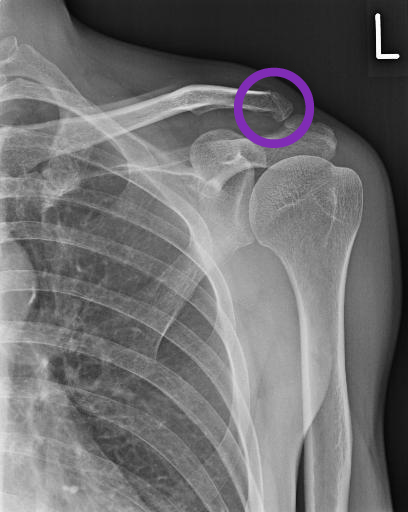

それではレントゲン撮りますね。ということでレントゲン技師の先生に導かれてレントゲン室に。2枚撮ったあとやはりマズいかも・・・という言葉があり、以前にも同じ所骨折しているのですよ。と話すと、その時の影が写っているかも知れないのでもう一枚撮りましょう。ということで再度別の角度から。

その後私の番となり、先生のところへ。「う~ん折れてるね。」

と言うことで見せてくれた写真がこれ。

受診後。先生にブログやFBに掲載したいからiPhoneで写真撮っていいですか?と言うとどこが分かりやすいかな?と言って角度を変えてそして、それならCDにデータにした方がよいだろ。と言ってわざわざCDにして頂きました。最近のテクノロジーは(笑)